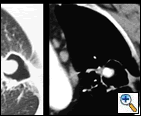

The patient was hemodynamically stable and his physical examination was unremarkable. His laboratory examination did not reveal any electrolyte abnormalities or anemia. An admission chest roentgenogram was obtained and revealed a LUL abnormality (Figure 1). Consequently, a computed tomogram (CT) was obtained and confirmed the LUL abnormality as a thick-walled 2 cm LUL cavity and also revealed the presence of a contrast enhanced, 7 mm mural, soft tissue nodule with the cavity (Figure 2). A high-resolution CT with three dimensional reconstruction demonstrated communication from the LUL nodule to vessels adjacent to the cavity wall (Figure 3).